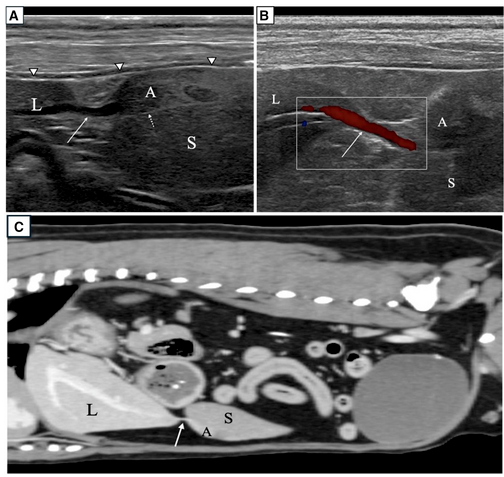

- 영상 진단 결과: 초음파 검사에서 비장 꼬리 부분과 명확히 구분되는 비정상적인 실질 구조물이 발견되었습니다. 컬러 도플러 초음파를 통해 이 구조물이 간의 좌측 외엽(Left lateral liver lobe)과 혈관 줄기로 연결되어 있음을 확인하였으며, CT 촬영을 통해 해당 혈관 줄기와 조영 증강 특성이 간 실질과 유사함을 최종 확증하였습니다.

유경성 부간엽은 줄기가 꼬이는 '염전(Torsion)'이 발생할 경우 급성 복통을 유발하는 응급 상황으로 이어질 수 있습니다. 하지만 본 증례처럼 염전이나 파열 같은 합병증이 없는 경우에는 비특이적인 영상학적 소견을 보일 수 있으므로, 도플러 초음파와 CT를 활용하여 간 실질과의 연결성을 확인하는 것이 정확한 진단에 필수적입니다. 이 연구는 복부 내 비정상 구조물에 대한 감별 진단 목록에 유경성 부간엽을 포함해야 함을 시사합니다.